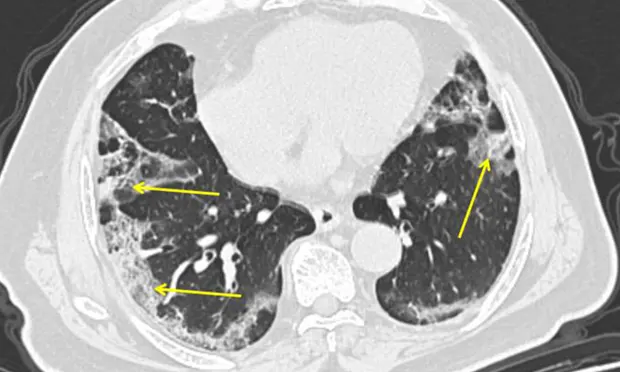

Врач-респиратор Джон Уилсон объясняет диапазон воздействия Covid-19. Это изображение показывает компьютерную томографию мужчины с Covid-19. Пневмония, вызванная новым тяжелым острым респираторным коронавирусом 2, может проявляться как характерные мутные пятна на внешних краях легких, обозначенные стрелками.

Врач-респиратор Джон Уилсон объясняет диапазон воздействия Covid-19. Это изображение показывает компьютерную томографию мужчины с Covid-19. Пневмония, вызванная новым тяжелым острым респираторным коронавирусом 2, может проявляться как характерные мутные пятна на внешних краях легких, обозначенные стрелками. То, что стало известно как Covid-19 или коронавирус, началось в конце 2019 года как группа случаев пневмонии с неизвестной причиной. Установлено, что причиной пневмонии является новый вирус - тяжелый острый респираторный синдром, коронавирус 2 или Sars-CoV-2. Болезнь, вызванная вирусом - Covid-19. В настоящее время объявленная Всемирной организацией здравоохранения (ВОЗ) пандемией, большинство людей, которые болеют Covid-19, страдают только легкими симптомами, напоминающими простуду. ВОЗ говорит, что около 80% людей с Covid-19 выздоравливают без какого-либо специального лечения. Только один человек из шести серьезно заболел и «с трудом дышит». Итак, как Covid-19 может развиться